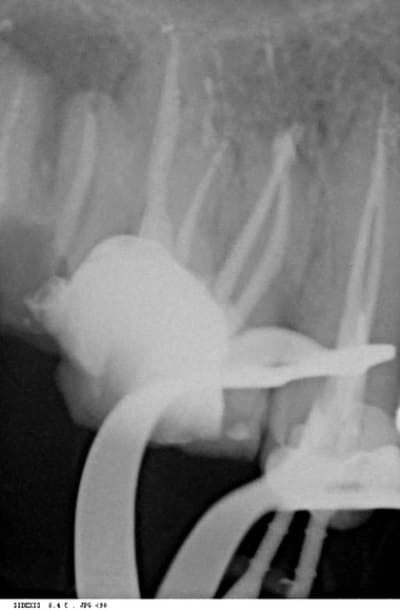

la perfo est en effet intracanalaire, elle démarre pile au niveau de la courbure apicale.

je regarde à nouveau cette radio,on voit la perf en distal,qui a suivi un chemin rectiligne plutot que de suivre la courbe de la dent,mais pourquoi cette autre broche entre les deux molaires?,ce n'est pas un canal,si je lis bien cette radio?

si la lime 1 est la plus a droite de laRX, le distal etantà G c'est la quelle qui te tracasse? la 1? la 4? tu situes la perfo où?

l'interrogation vient du cone le plus a droite de la radio! la perf indiquée par un rond!

mais surtout, tu ne vois pas l'apex?

non annie, il y a une perf, elle est sur le mv1, c'est tout.

oui,justement dans la mauvaise direction,ne suit pas la courbe du canal

sur la broche entre les deux molaires? non pas vraiment

annie, ou vois-tu une broche entre deux molaires?

Sur ta radio la broche a l'extrème droite ,

c'est le canal palatin, annie. c'est le canal palatin.

regarde bien cette broche a l'interieur de l'ovale du clamp,il n'y a pas de dent autour!

ou c'est ta radio,ou mes yeux,pourquoi tes racines me sont elles invisibles?

voilà une radio avec une autre incidence: tu vois le canal palatin? tu vois l'obturation dedans? non?